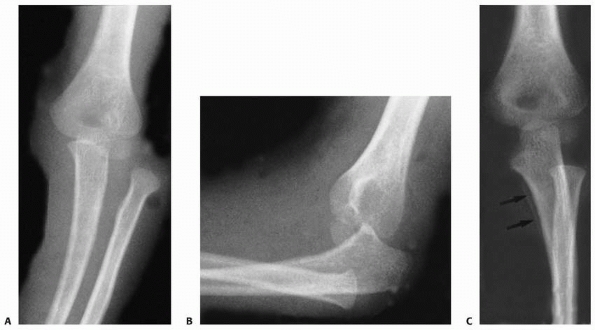

FIGURE 16-6 Radiographic findings. A.

Anteroposterior radiograph. The radial head is superimposed behind the distal humerus. There is increased cubitus valgus. The medial epicondyle has not been avulsed. B. Lateral radiograph demonstrating that the proximal radius and ulna are both displaced posteriorly to the distal humerus. |